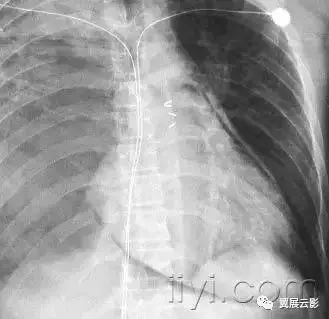

五十六、气胸和张力性气胸

病理:气胸指胸膜腔内出现气体。包括自发性、外伤性、诊断性和张力性气胸。张力性气胸是指胸膜腔内气体积聚,具有一定的压力。正常情况下,以此肺会完全压缩塌陷,而在顺应性减低的肺,可以保持膨胀不全。

平片和CT:在胸片上,可以看到脏层胸膜边,图55,除非气胸量很少,或者胸膜边缘与x线不呈切线位。张力性气胸可以出现明显的纵隔移位和/或一侧膈压低。一些非张力性气胸也可以出现纵隔移位,这是由于病变侧胸膜腔内压力达到大气压,而健侧胸膜腔压力为负造成的。